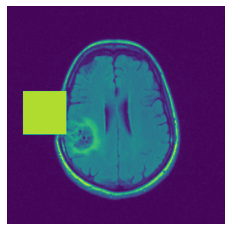

2.2 Self-supervised Intelligent Masking

Each self-supervision task is composed of two steps: 1) creating paired input-output images and 2) training a prediction model to learn the mapping. In the first step, for a given sample 𝐱𝐢subscript𝐱𝐢\mathbf{x_{i}} from dataset 𝐗={𝐱𝟏,𝐱𝟐,,𝐱𝐧}𝐗subscript𝐱1subscript𝐱2subscript𝐱𝐧\mathbf{X}=\{\mathbf{x_{1}},\mathbf{x_{2}},\dots,\mathbf{x_{n}}\}, we produce an occluded variant 𝐱~𝐢subscript~𝐱𝐢\mathbf{\tilde{x}_{i}}, and then train a prediction model to learn the inverse mapping of 𝐱~𝐢𝐱𝐢subscript~𝐱𝐢subscript𝐱𝐢\mathbf{\tilde{x}_{i}}\rightarrow\mathbf{x_{i}}. As shown in Fig 1, we introduce an intelligent masking mechanism to occlude a region based on the input image context to improve the semantic features learned by the prediction model and its performance on subsequent downstream tasks. In the following sections, we present the masking and prediction methods in detail.

Refer to caption

Figure 1: Overview of the proposed model. In the masking network (upper part), the agent selects a patch of the image to be occluded based on its reward estimation of masking each patch. The original image is occluded with the output mask created by the agent. Then, the prediction network (lower part) predicts the occluded region.

In figure 3, we present qualitative examples of different masking strategies. It is observed that, unlike context prediction and restoration, our method tends to propose targeted masks like the tumor regions or regions with abnormalities and avoids masking less helpful regions. However, it should be noted that Intelligent-Masking does not necessarily mask the tumor regions but considers all areas of interest that results in better feature learning. Examples of other masking samples are provided in supplementary materials. Furthermore, in medical images, unlike natural scenes, the structures are very local with imbalanced information throughout an image. Therefore, random masking strategies as shown in Fig 3 operate ineffectively by masking non-informative regions.

(a) Original

(b) Intelligent-Masking

(c) Context Prediction

(d) Context Restoration

Figure 2: Qualitative examples of compared method’s strategies for masking